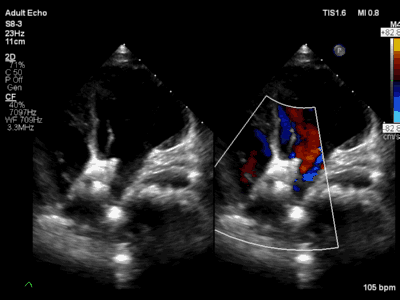

超声心动图提示伞盘位置良好无残余分流后,进一步逆时针旋转控制手柄,解脱输送钢缆和封堵器栓头的连接,释放封堵器。

术后经胸超声心动图提示封堵器位置稳定,房间隔分流消失,封堵器不干扰心脏瓣膜等心内结果,手术效果满意。